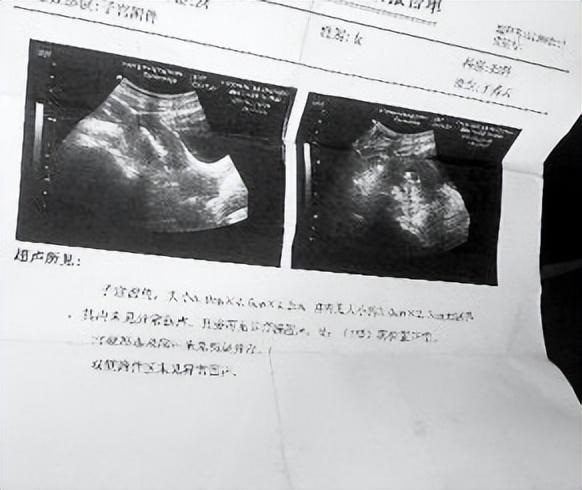

可是等到检查结束之后,报告的内容却让王世芬匪夷所思,因为检查报告里显示王世芬已经怀孕了。

可是接下来发生的事情,更是让陈艳和王世芬都陷入到了巨大的震惊当中,因为在来到大医院检查之后,结果显示王世芬确实并没有怀孕。

但是真实结果却让他们二人无法接受,因为王世芬患上了子宫肌瘤,由于瘤体较大所以才会被误以为成怀孕了。

得知结果的王世芬感到世界一片昏暗,因为他知道子宫肌瘤的严重性,轻则失去生育能力,重则很有可能因此丧命。